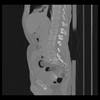

36 CUERPO,CE,Sagittal,3.000,CUERPO,Sagittal,